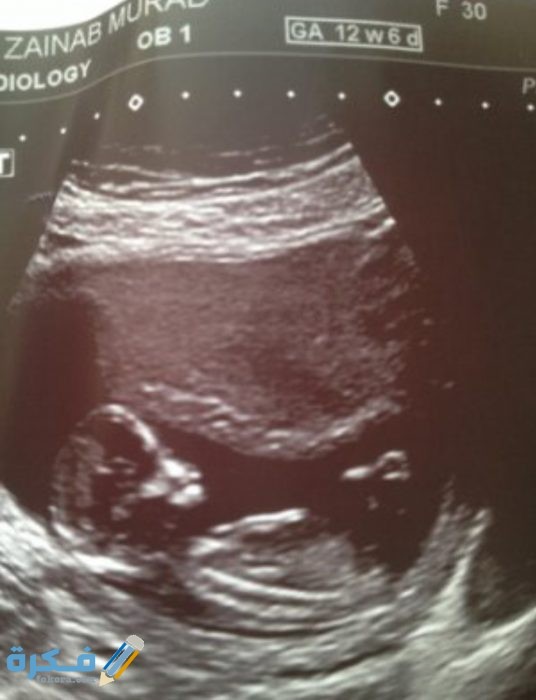

شكل الجنين في السونار :

يختلف السونار الخاص بالولد والبنت والاختلافات هي :

- قديما اعتمد الناس في التعرف على نوع جنس الجنين من خلال طرق تقليدية متعددة قد توضح الطرق نوع الجنين بشكل صحيح ولكنها قد تخطئ في بعض الأحيان ، ولكن مع مرور الوقت ظهرت الأجهزة الحديثة منها السونار وغيرها من الأجهزة الأخري التي تثبت بكفاءة نوعية الجنين .

الجنين الذكر

- يتم معرفة نوع الجنين في الشهر الرابع من الحمل لأن الذي يميز الذكر في السونار وجود شئ يشبه السلحفاة بين قدمي الجنين وهو العضو الذكري وكلما كان واضحا ومنتصبا أكد ذلك علي نوعية الجنين بشكل دقيق .

الجنين الانثى

- عندما يكون الجنين انثى يجد الأطباء صعوبة في تحديد النوع وذلك لعدم وضوح العضو التناسلي الخاص بالأنثى والذي غالبا ما يشبه شطيرة الهمبرجر حيث أن لأن الشفرتين يشبهان طبقتي الخبز والبظر يشبه شريحة اللحم الموجودة وسط الشطيرة .